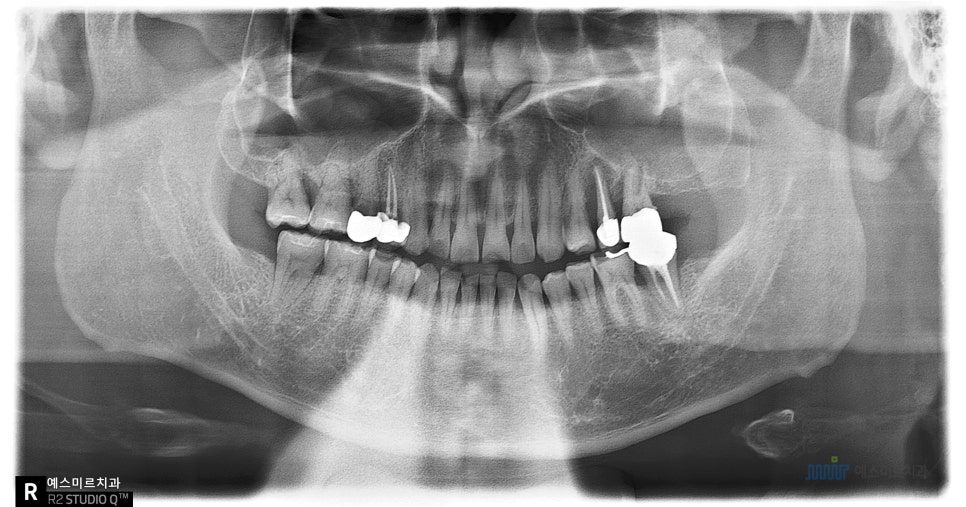

📍 내원 당시 상태

환자분은 왼쪽 위아래 치아가 흔들리고,

잇몸이 붓고 통증이 심하다며 내원하셨습니다

파노라마, 3D CT 정밀 촬영을 통해

검사를 진행해보니

👉 왼쪽 위쪽 상악동(코 옆 공기주머니)에

염증이 가득 차 있고,

뼈도 많이 녹아 있는 상태였습니다

왼쪽 치료 전, 오른쪽 치료 후